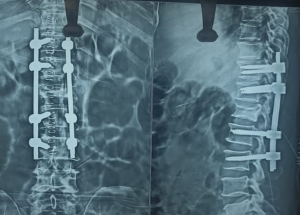

Expert spine services including minimally invasive surgery, pain management, and deformity correction.